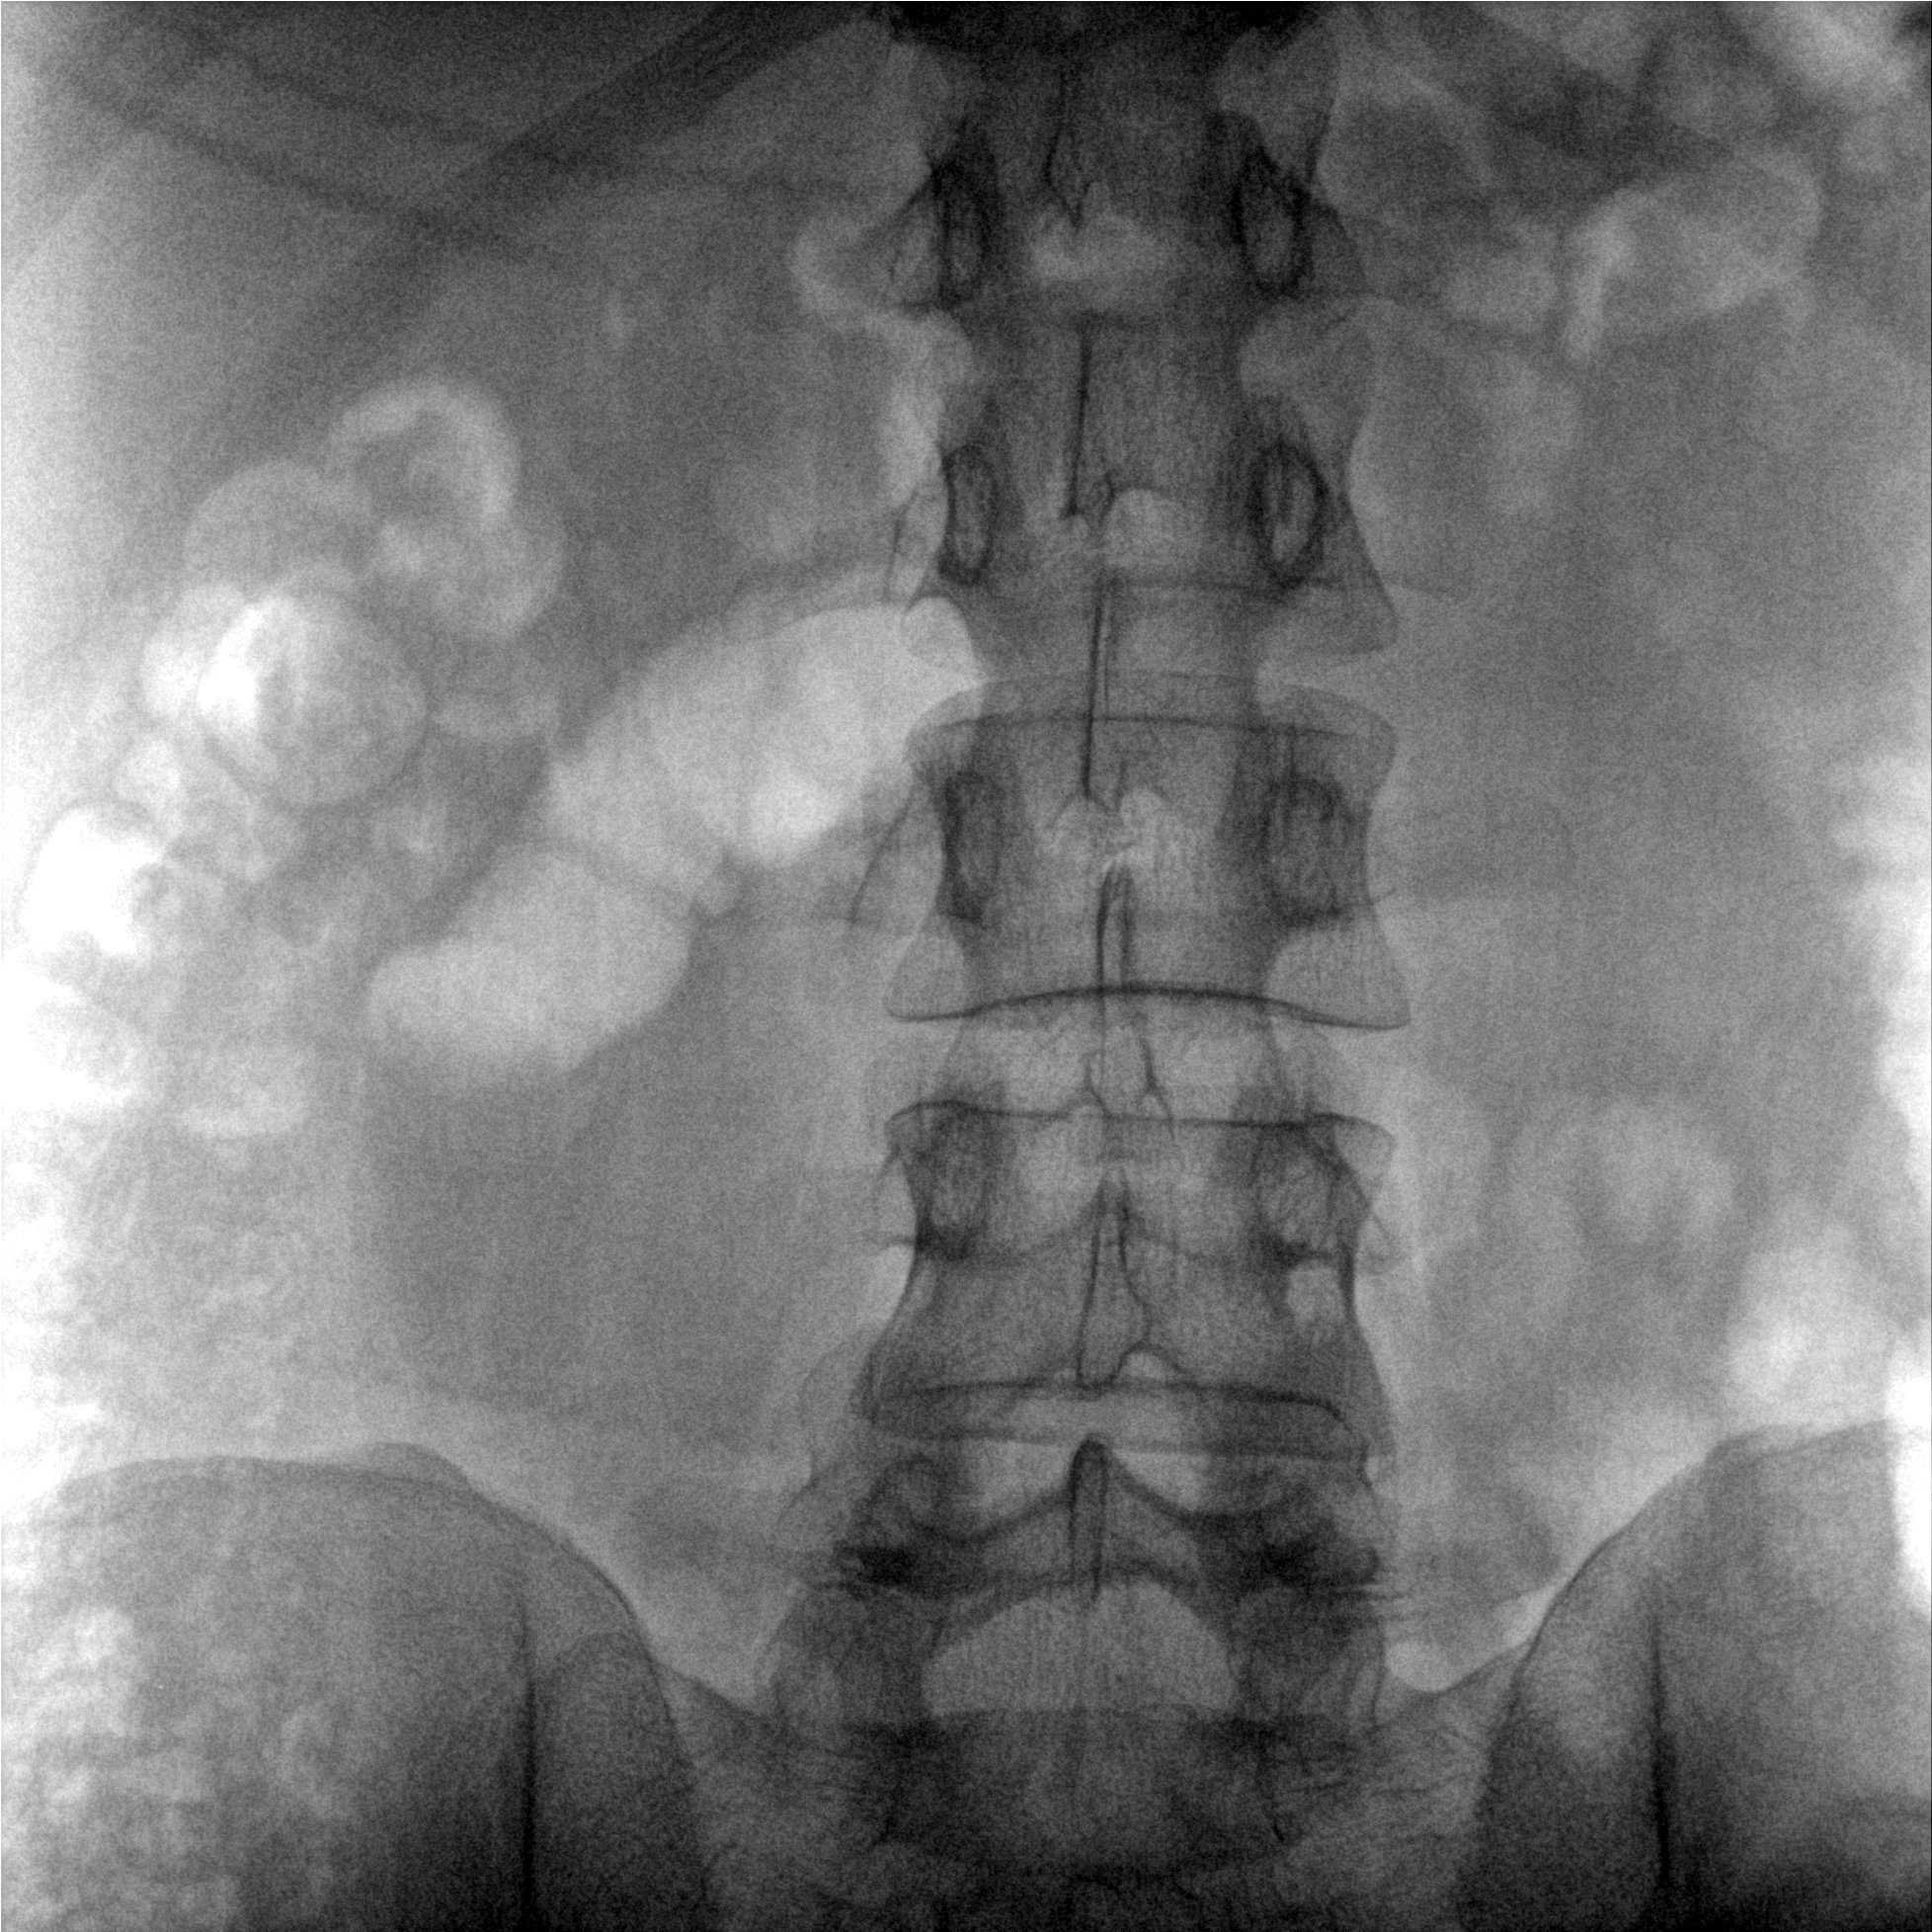

成像清晰、操作簡易、擺位便捷,主要適用于骨科、脊柱外科、矯形外科、創傷骨科及手術室等,能大幅度提升手術水準,降低手術風險和并發癥的概率。

提供更大的術中三維成像視野,采集更多圖像信息,可一次拍全全段頸椎、全段腰椎、七節胸椎、雙側骶髂關節、股骨頭及單側盆骨。